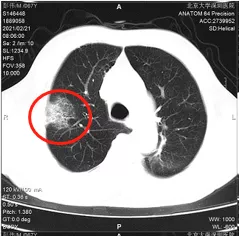

20幾年前,阿叔為了家人和自己的身體健康,狠下心把煙戒了,但卻萬沒想到,本來以為自己及時止損,癌症就不會找上門,但往往天不遂人願,去年因為長期乾咳總是不見好轉,阿叔就去了趟醫院做了檢查,CT結果出來後阿叔和家人都比較納悶和不解,怎麼會這樣?

肺腺癌中晚期

醫生根據阿叔的身體狀況和腫瘤發展程度,制定了化療+免疫治療的抗腫瘤方案,化療用來對付正在發展中的腫瘤,遏制它生長快速擴散,就好比阿叔肺部有一團小火苗越燒越旺,先用一盆冷水澆下去讓它冷靜冷靜,阻止它上竄的勢頭,再用免疫治療和腫瘤打拉鋸消耗戰,磨死腫瘤。

讓人驚喜的是,這套組合拳果然很有用,打的腫瘤非常狼狽,不到半年的治療時間,腫瘤竟然消失了!當然我在這說消失肯定不算,PET-CT也顯示阿叔身上一點腫瘤都沒有!

本來,讓阿叔一家san值狂掉的腫瘤,經過治療之後消失是件高興地事兒,之後有發現有淋巴結,經過放療後也成功幹掉了,可複查的時候新的問題又出現了。

雙肺開始出現不明原因的病灶,並且開始有纖維化的趨勢,啥意思?就是說完全纖維化的部分基本永遠失去了肺部該有的功能,所以治療要抓緊。

為了排除這些疑惑,CT片子先交給了影像科很權威的專家檢視,排除了放射性肺炎。